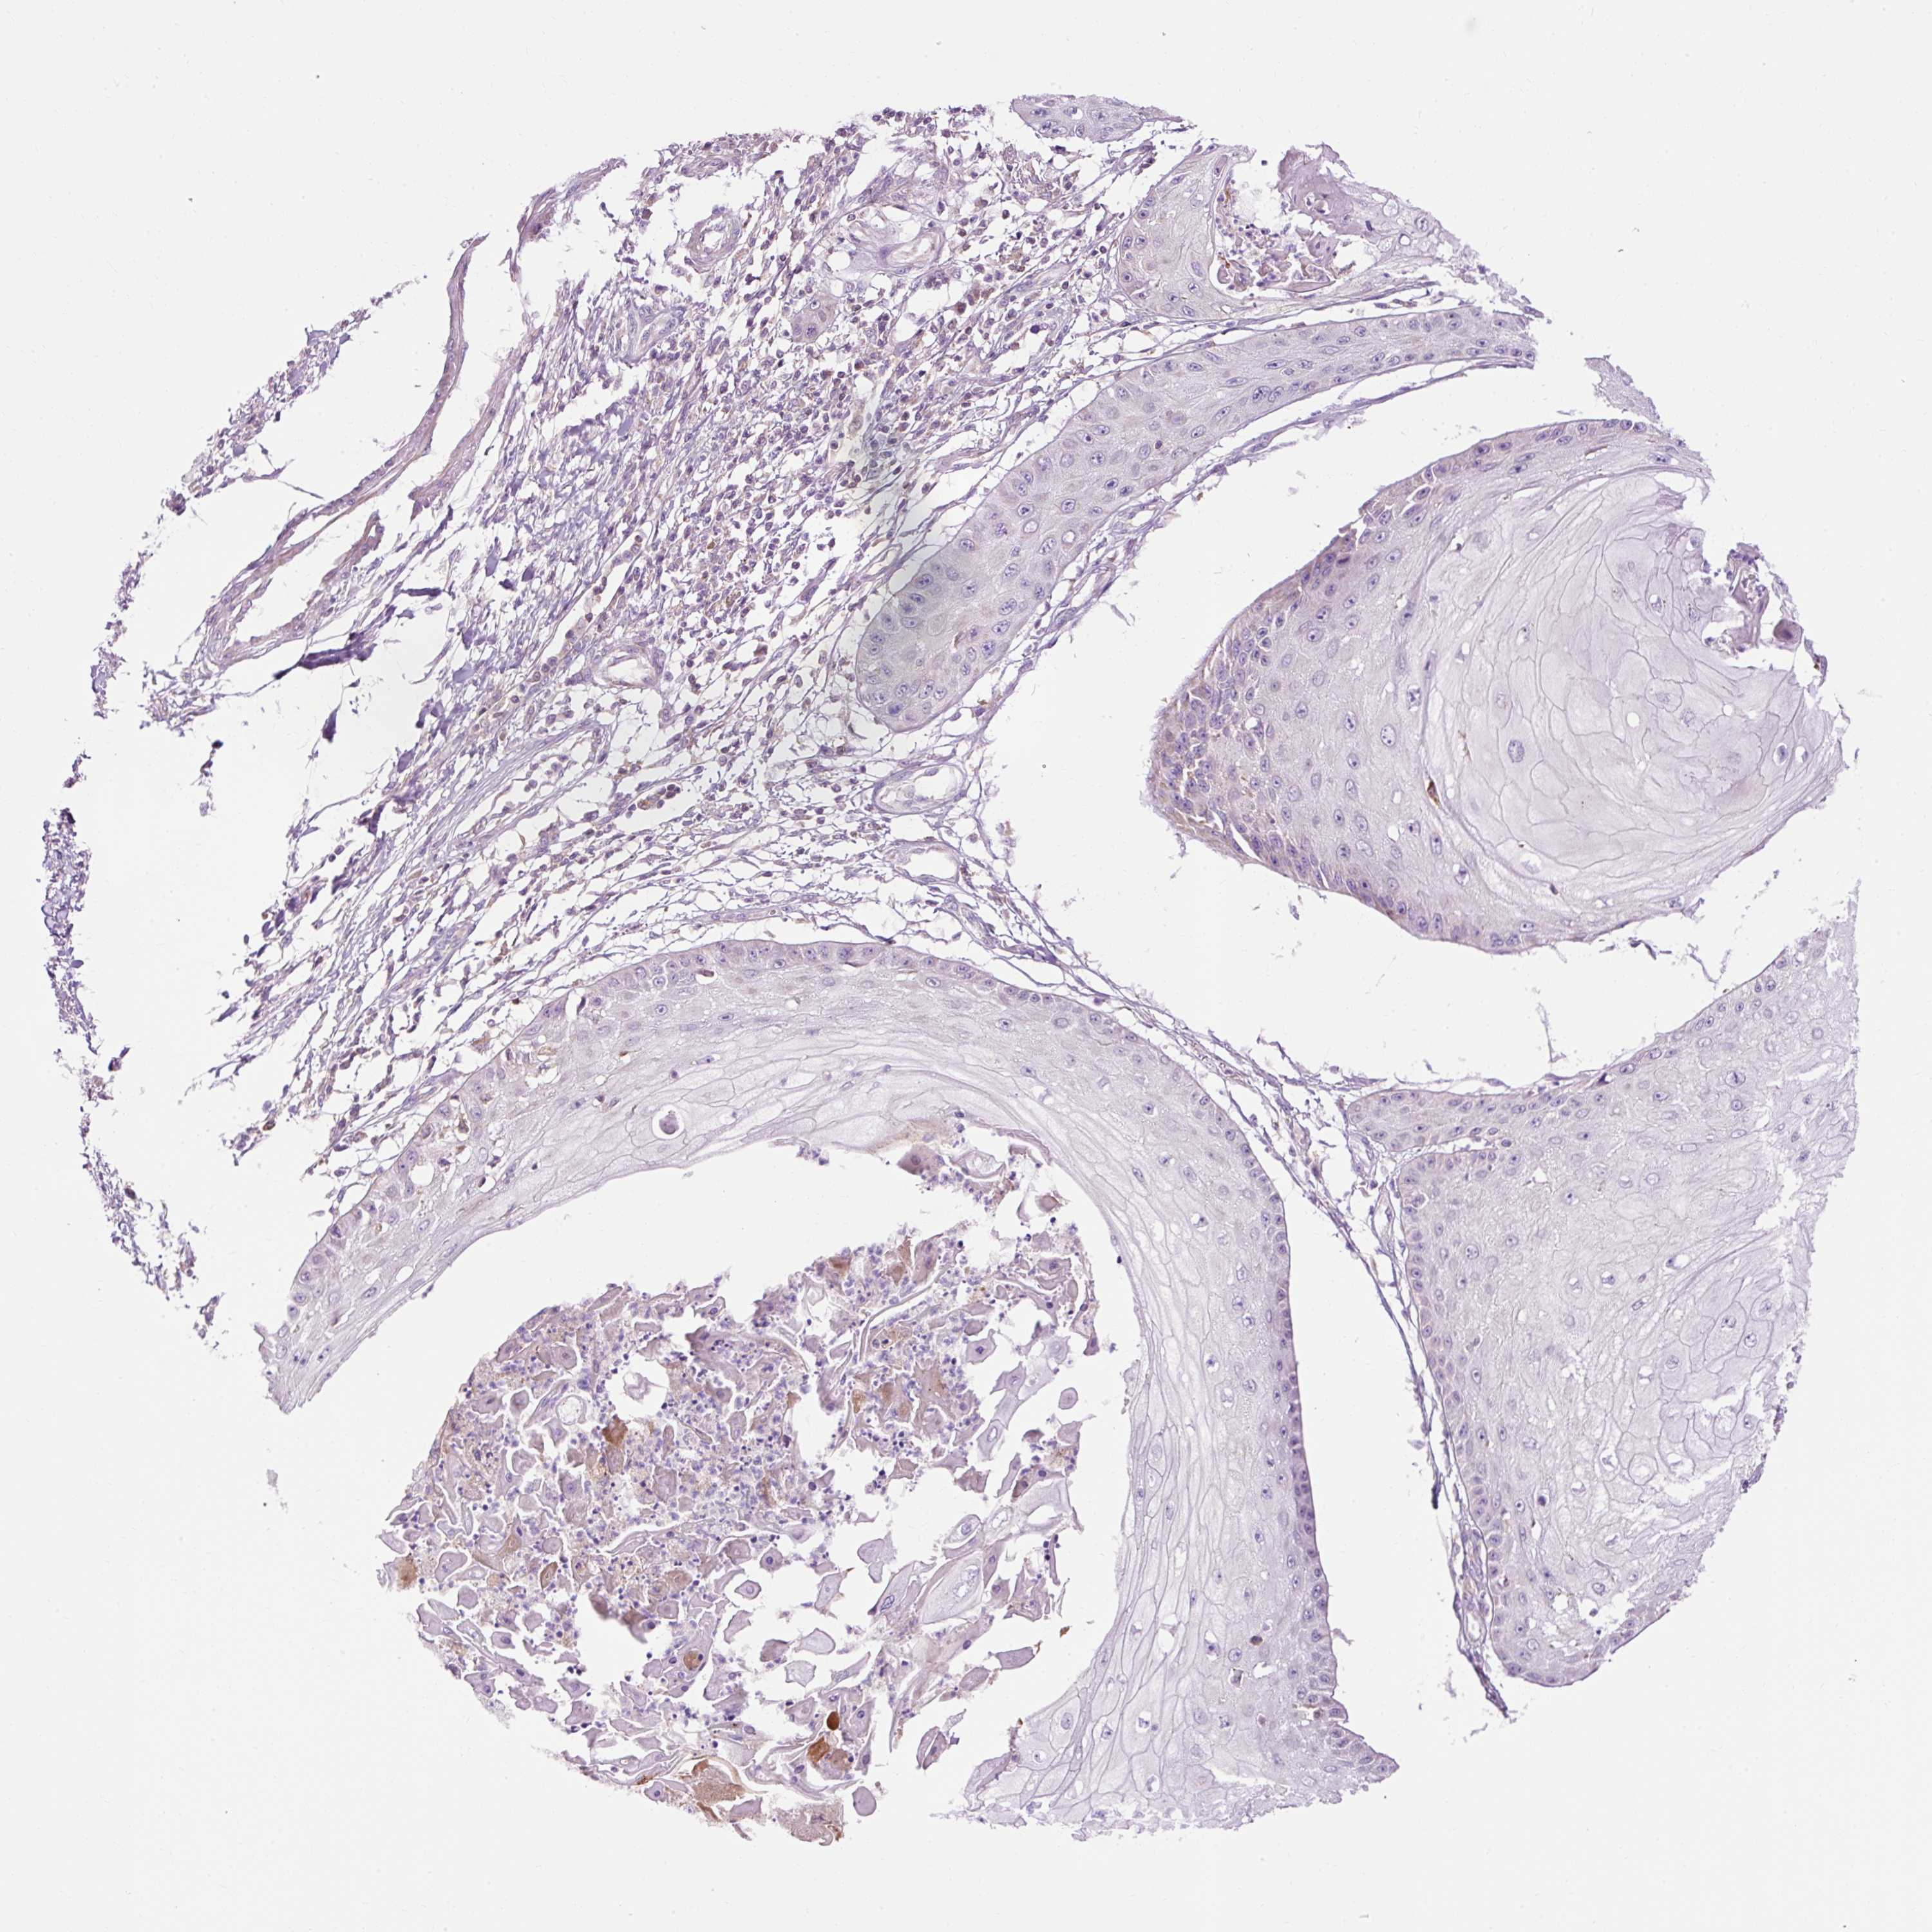

Basal cell and squamous cell cancer

SKIN CANCER - Protein expressioni

A mouse-over function shows sample information and annotation data. Click on an image to view it in a full screen mode. Samples can be filtered based on level of antibody staining by selecting one or several of the following categories: high, medium, low and not detected. The assay and annotation is described here.

Antibody stainingi

Antibody staining in the annotated cell types in the current human tissue is reported as not detected, low, medium, or high, based on conventional immunohistochemistry profiling in selected tissues. This score is based on the combination of the staining intensity and fraction of stained cells.

Each image is clickable and will lead to virtual microscopy that enables deeper exploration of all samples and also displays staining intensity scores, fraction scores and subcellular localization as well as patient and tissue information for each sample.

Basal cell carcinoma

Squamous cell carcinoma, NOS

Squamous cell carcinoma, metastatic, NOS